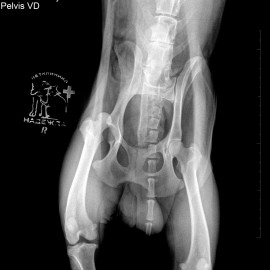

Наш пациент собака по кличке Барни.

После автотравмы перестал вставать на заднюю правую лапу. После проведенных обследований был поставлен диагноз - вывих правого тазобедренного сустава. Была проведена операция: остеосинтез правого тазобедренного сустава. При операции для стабилизации сустава установлен протез круглой связки.

Снимок 1 до операции.